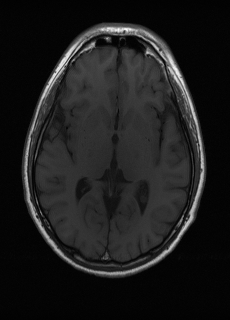

Sequence LR SISO MIMO MIMO tuned GT

λT1=6.63subscript𝜆subscript𝑇16.63\lambda_{T_{1}}=6.63 Refer to caption (a) 35.46/0.9431 Refer to caption (b) 40.82/0.9826 Refer to caption (c) 41.84/0.9857 Refer to caption (d) 42.12/0.9867 Refer to caption (e) PSNR/SSIM

λT2=2.11subscript𝜆subscript𝑇22.11\lambda_{T_{2}}=2.11 Refer to caption (f) 32.34/0.9254 Refer to caption (g) 36.19/0.9699 Refer to caption (h) 36.42/0.9711 Refer to caption (i) 36.78/0.9695 Refer to caption (j) PSNR/SSIM

λflair=8.00subscript𝜆𝑓𝑙𝑎𝑖𝑟8.00\lambda_{flair}=8.00 Refer to caption (k) 42.54/0.9489 Refer to caption (l) 45.24/0.9837 Refer to caption (m) 45.89/0.9868 Refer to caption (n) 46.35/0.9880 Refer to caption (o) PSNR/SSIM

Figure 4: Visual comparison of different recovery methods on real data